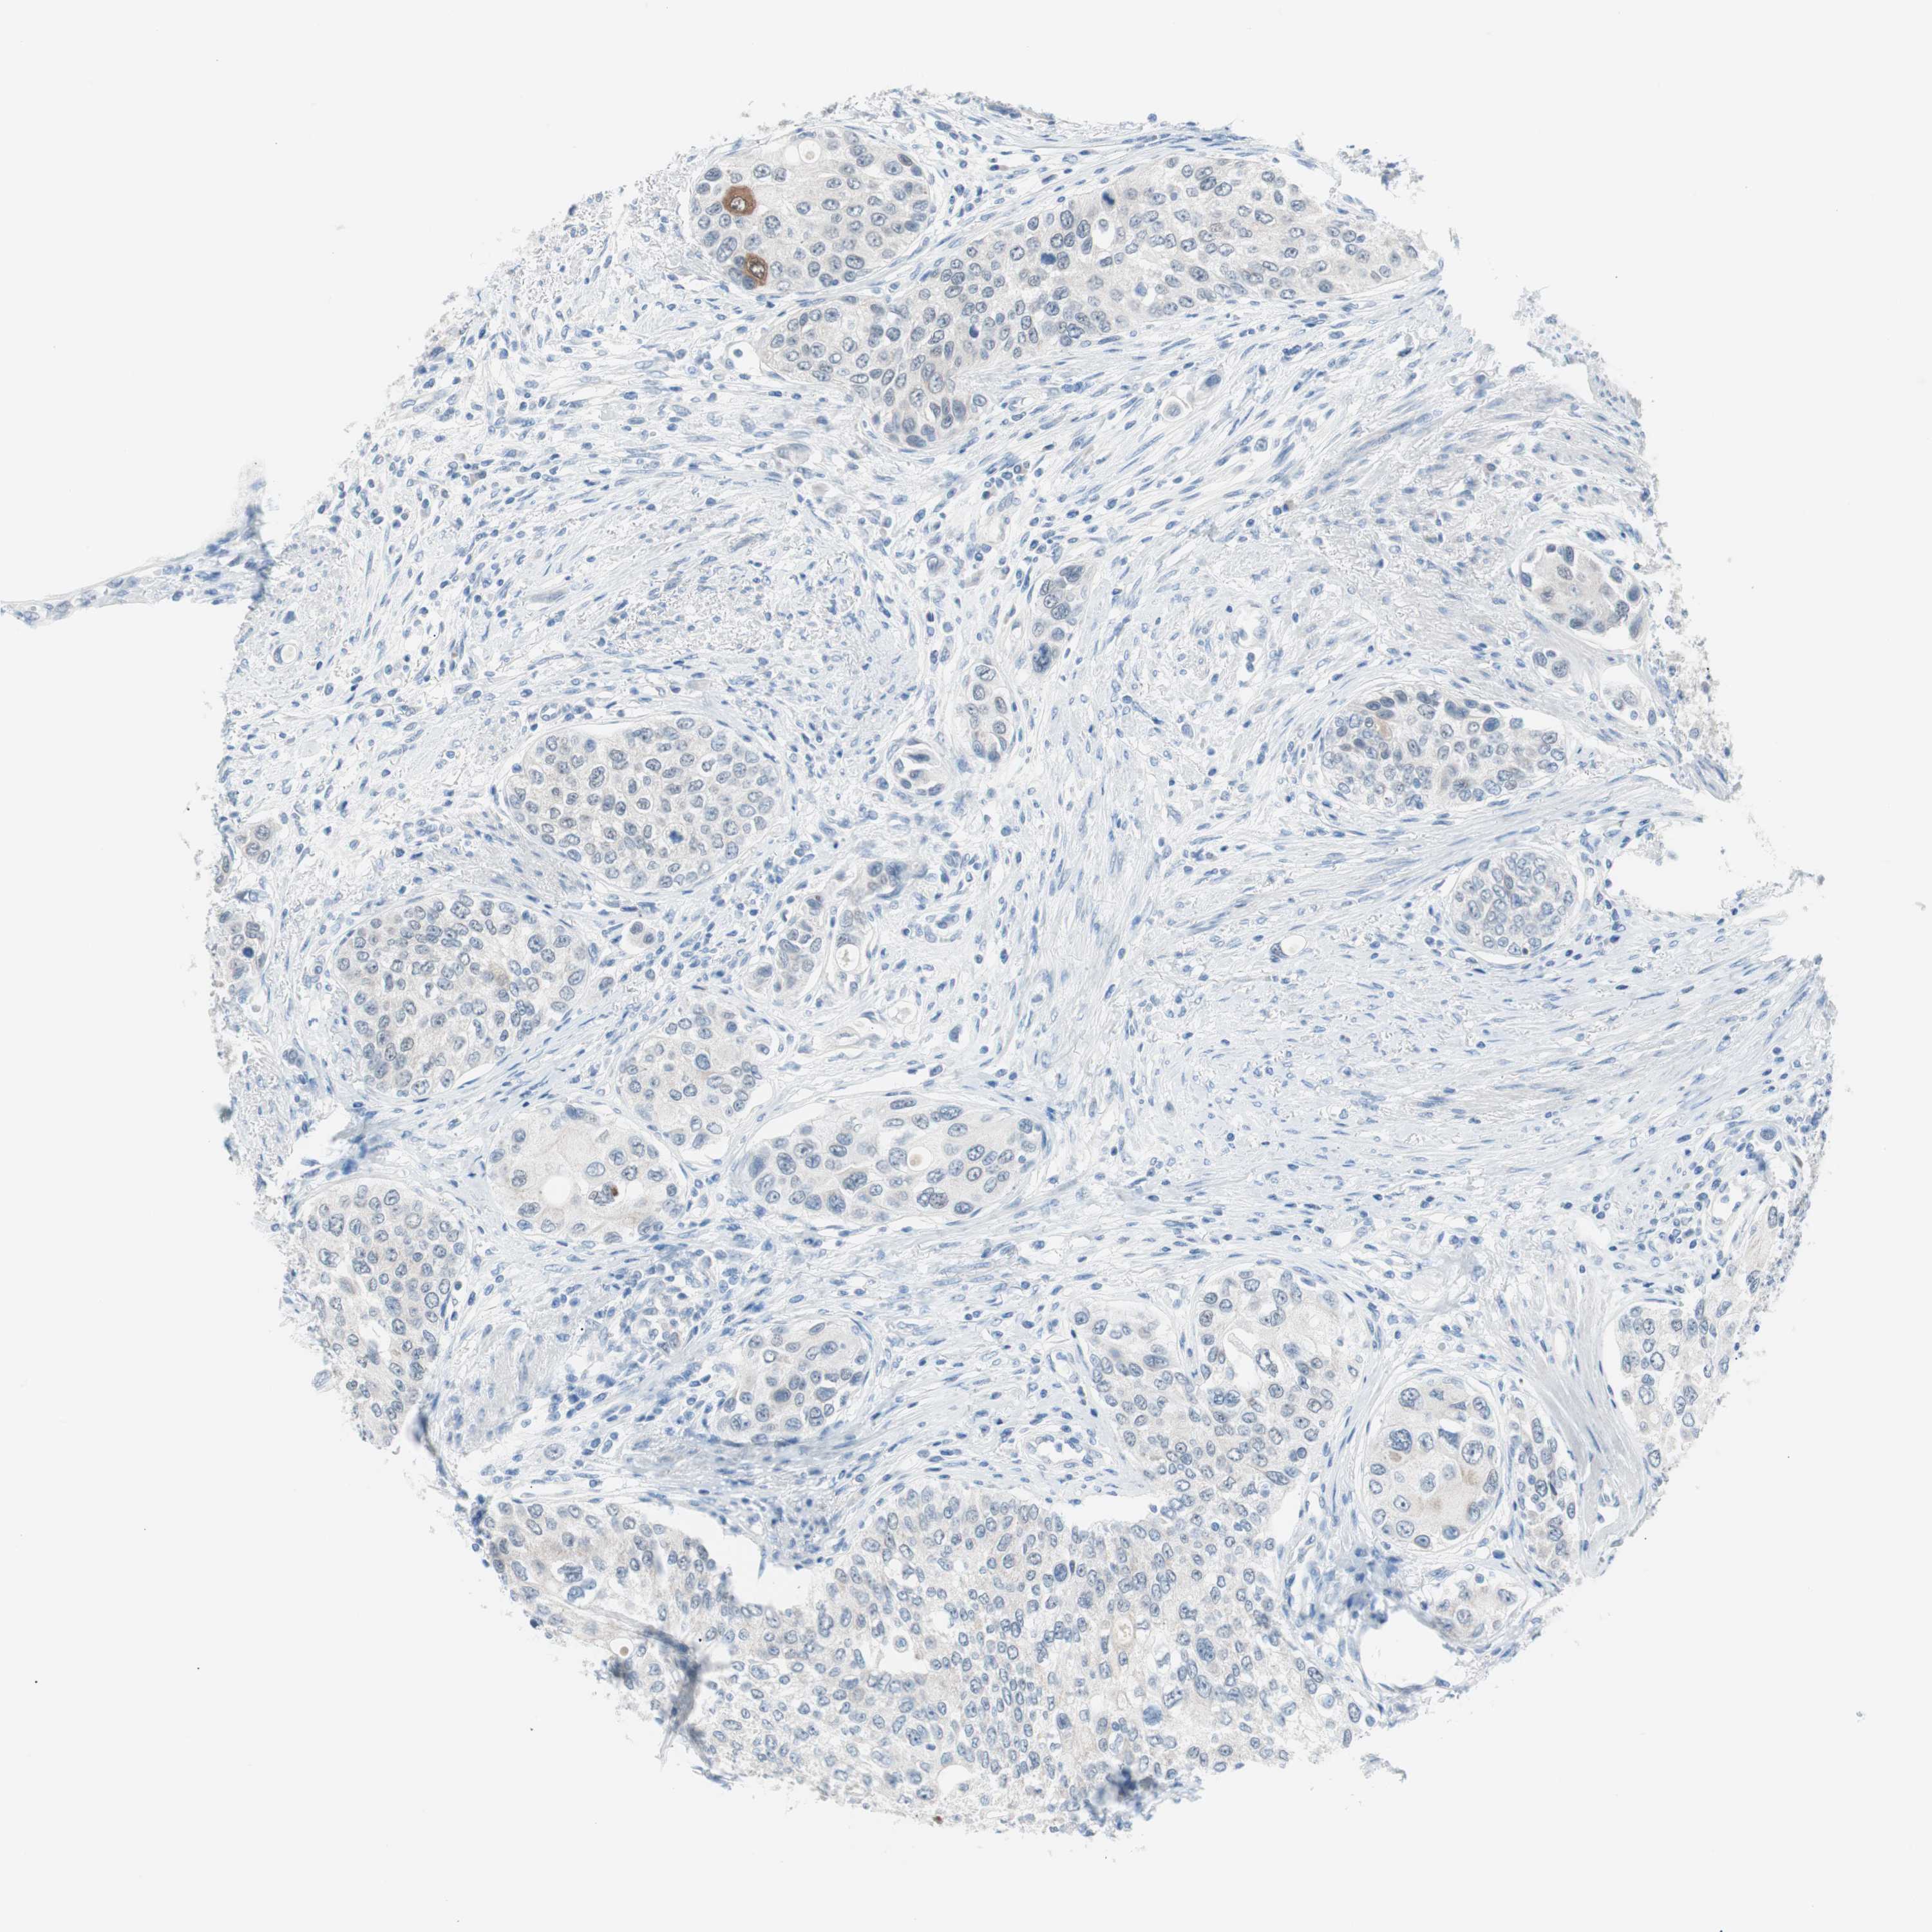

UROTHELIAL CANCER - Protein expressioni

A mouse-over function shows sample information and annotation data. Click on an image to view it in a full screen mode. Samples can be filtered based on level of antibody staining by selecting one or several of the following categories: high, medium, low and not detected. The assay and annotation is described here.

Note that samples used for immunohistochemistry by the Human Protein Atlas do not correspond to samples in the TCGA dataset.

Antibody stainingi

Antibody staining in the annotated cell types in the current human tissue is reported as not detected, low, medium, or high, based on conventional immunohistochemistry profiling in selected tissues. This score is based on the combination of the staining intensity and fraction of stained cells.

Each image is clickable and will lead to virtual microscopy that enables deeper exploration of all samples and also displays staining intensity scores, fraction scores and subcellular localization as well as patient and tissue information for each sample.

Antibody HPA006884

Antibody HPA006885

Antibody CAB002452

Urothelial carcinoma, Low grade

Urothelial carcinoma, High grade

Adenocarcinoma, NOS